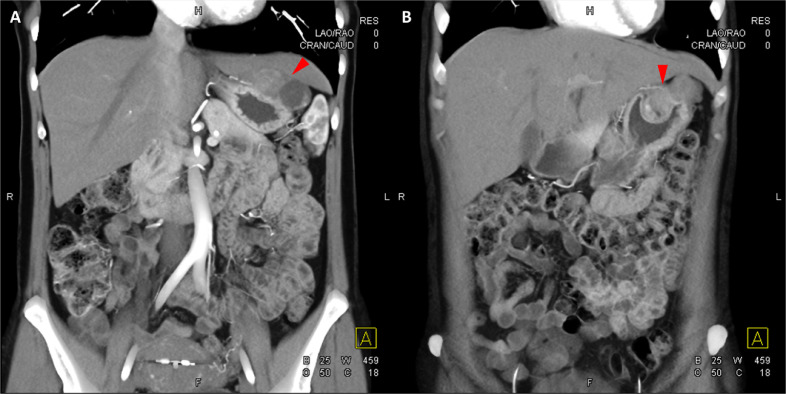

颈部增强 CT 显示 2 个强烈强化的肿块。 一个位于颈部右侧,位于右侧颈内动脉后方的颈动脉间隙中,位于茎突内侧,大小为 24 × 24 × 30 mm,颈静脉横向移位(图 1A)。 第二个位于左侧颈动脉间隙,在分叉处正上方展开颈外动脉和颈内动脉,尺寸为 15 × 18 × 22 mm(图 1B)。 影像学检查结果与右侧迷走神经和左侧颈动脉体副神经节瘤一致,与之前的活检结果一致。

图1:右侧迷走神经和左侧颈动脉体副神经节瘤。 (A) 轴位增强 CT 显示右侧颈动脉间隙、右侧颈内动脉后方(白色箭头)和茎突内侧有强烈强化的肿块(红色箭头)。 (B) 轴位对比增强 CT 显示左颈动脉间隙有强烈强化的肿块(红色箭头),向后张开颈内动脉(红色箭头),向前张开颈外动脉(红色箭头)。 (C) 冠状对比增强 CT 显示两个增强肿块(红色箭头)。